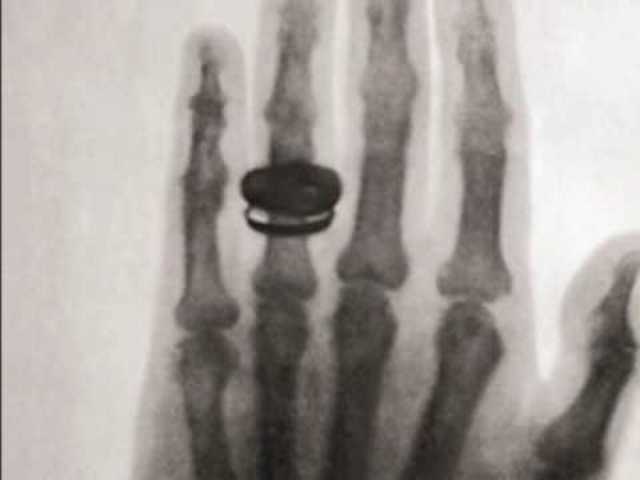

• The First X-ray

The First X-ray

Dr. Wilhelm Conrad Rōntgen used the first X-ray